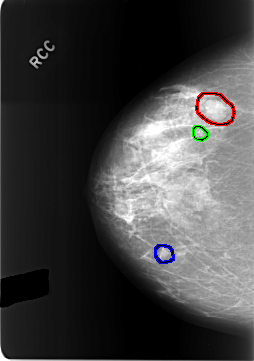

FILE: C_0304_1.RIGHT_MLO.OVERLAY

TOTAL_ABNORMALITIES 3

ABNORMALITY 1

LESION_TYPE MASS SHAPE LOBULATED MARGINS CIRCUMSCRIBED

ASSESSMENT 3

SUBTLETY 5

PATHOLOGY BENIGN

TOTAL_OUTLINES 1

BOUNDARY

ABNORMALITY 2

LESION_TYPE CALCIFICATION TYPE AMORPHOUS DISTRIBUTION CLUSTERED

ASSESSMENT 4

SUBTLETY 4

ABNORMALITY 3

LESION_TYPE MASS SHAPE OVAL MARGINS OBSCURED